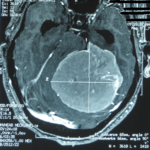

Cette masse peut entrainer notamment :

- Une irritation du cerveau qui se manifeste par une épilepsie

- Une compression voire destruction d’une partie du cerveau causant un affaiblissement ou une perte d’une fonction du cerveau

- Une augmentation de la pression à l’intérieur du crâne (espace inextensible à l’intérieur duquel vient s’ajouter le volume de la tumeur), ce qui va se manifester initialement par des maux de tête d’aggravation progressive qui vont s’associer à des nausées, des vomissements, des troubles visuels… Cet état peut aboutir à la perte de la vue dans les formes d’évolution lente et au décès dans les formes d’évolution rapide.